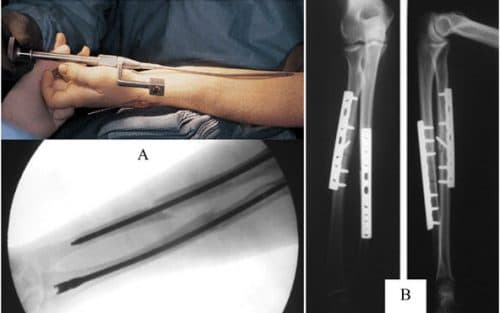

Chị Ngọc Dương thân mến! Gẫy tay bao lâu tháo bột được là quan tâm hàng đầu của những người bị gãy tay. Thông thường gãy tay sẽ phải bó bột khoảng 6 – 8 tuần. Thời gian tháo bột nhanh hay chậm phụ thuộc vào mức độ nặng – nhẹ của tình trạng gãy xương. Nếu xương gãy và còn bị dập, thời gian lành sẽ lâu hơn, đồng nghĩa với thời gian bó bột sẽ kéo dài hơn.

Thời gian tháo bột nhanh hay chậm phụ thuộc vào mức độ nặng – nhẹ của tình trạng gãy xương.